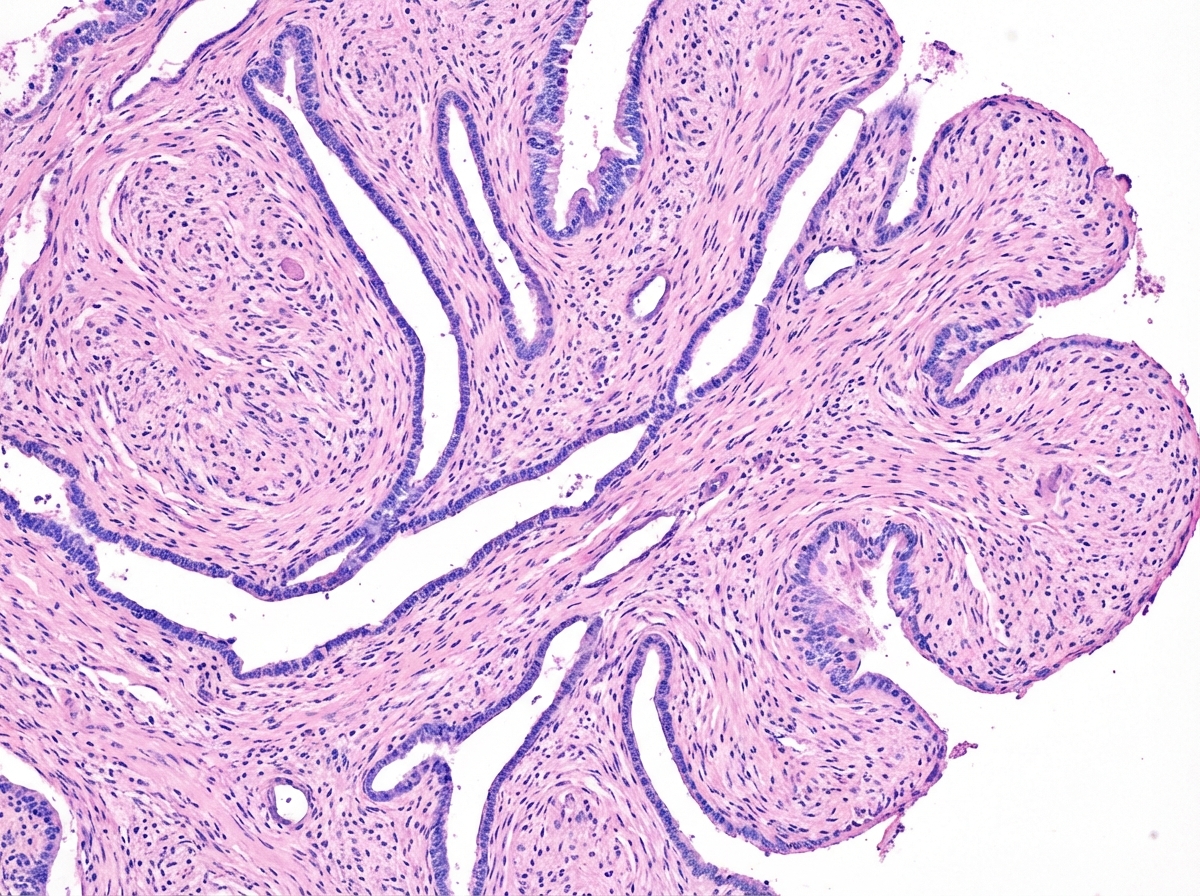

A 48-year-old woman comes to the physician for the evaluation of a left breast mass that she noticed 4 weeks ago. It has rapidly increased in size during this period. Vital signs are within normal limits. Examination shows large dense breasts; a 6-cm, nontender, multinodular mass is palpated in the upper outer quadrant of the left breast. There are no changes in the skin or nipple. There is no palpable cervical or axillary adenopathy. Mammography shows a smooth polylobulated mass. An image of a biopsy specimen is shown. Which of the following is the most likely diagnosis?